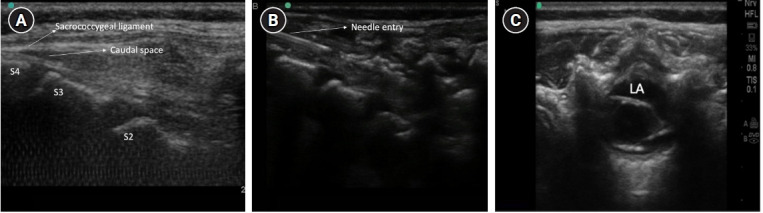

小儿区域麻醉(RA)已成为小儿麻醉中发展迅速的一个领域,需要不断地获取知识。这篇综述强调了这一专科的当代意义,重点是其在新生儿和婴儿中的应用。RA 的主要目的是在有效解决围术期疼痛的同时保持微妙的生理平衡,从而提高对患者的整体护理。本综述探讨了 RA 在这一年龄组中的优势。此外,还通过探讨传统和最新引入的 RA 技术的优缺点,对这些方法进行了研究。目的是让临床医生对这些方法在不同临床情况下的适用性有一个细致入微的了解。此外,本综述还阐明了与小儿 RA 相关的独特考虑因素,承认小儿患者具有独特的解剖和生理特点。还考虑了先天性异常的特殊病例及其对选择 RA 的影响。该综述的一个重点是新生儿和婴儿的局麻药剂量和各种阻滞所需的容量。还考虑了持续输注的剂量和输注的实际问题。还介绍了 RA 引起的并发症及其预防和治疗方法。这篇综述为各种区域阻滞的选择标准提供了实用的见解,有助于麻醉医生根据患者的不同需求做出明智的决定。

Pediatric regional anesthesia (RA) has emerged as a rapidly advancing dimension within pediatric anesthesia, demanding a continual commitment to knowledge acquisition. This review underscores the contemporary significance of this specialty, focusing on its application in neonates and infants. The primary objective of RA is to address perioperative pain effectively while preserving the delicate physiological balance, thereby enhancing overall patient care. This review explores the advantages offered by RA in this age group. Furthermore, conventional, and recently introduced techniques of RA are examined by exploring the advantages and disadvantages of these methods. The aim is to provide clinicians with a nuanced understanding of their applicability in different clinical scenarios. Additionally, the review elucidates the unique considerations associated with pediatric RA, acknowledging pediatric patients' distinctive anatomical and physiological characteristics. The exceptional cases of congenital anomalies and their implications for the choice of RA are considered. An aspect of the review is its focus on dosages of local anesthetics and the volumes required for various blocks in neonates and infants. The dosages for continuous infusion and practical issues with infusions are considered. Complications due to RA are described with their prevention and treatment. The review offers pragmatic insights into the selection criteria for various regional blocks, aiding anesthesiologists in making informed decisions tailored to individual patient needs.